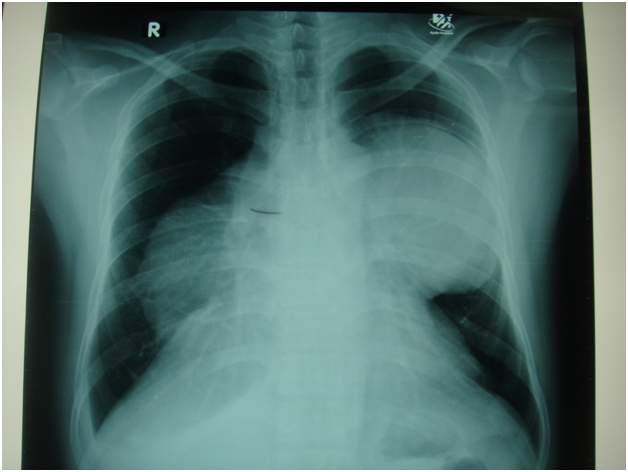

Figure 8 Preoperative (right) and postoperative(left) x-ray of huge Teratoma( mature cystic teratoma).